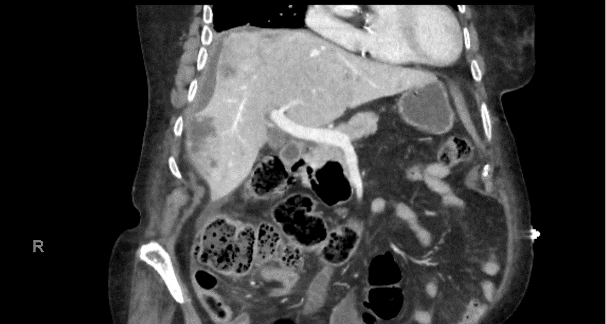

Une patiente de 90 ans consulte les urgences en raison de douleurs abdominales et de vomissements. L’abdomen est diffusément douloureux, particulièrement en hypochondre droit. Le bilan biologique montre un important syndrome inflammatoire avec des leucocytes à 33 G/L et une CRP à 250 mg/L, sans perturbation des tests hépatiques. Un CT-scanner abdominal est effectué.

Le radiologue retient des probables abcès hépatiques en raison du syndrome inflammatoire sans exclure un diagnostic différentiel de métastases. La patiente est hospitalisée pour antibiothérapie iv.